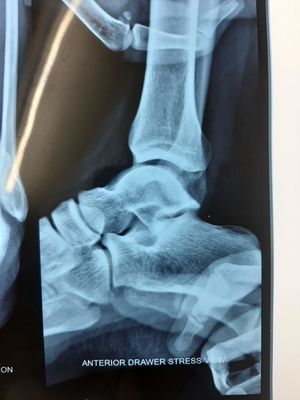

Showing topics for - Ankle instability

Don\\\'t underestimate simple ankle sprain?

Approx 20 to 40 percent patient after simple ankle sprain develop chronic ankle instability.  This is how we treat this surgically?? This is an e...